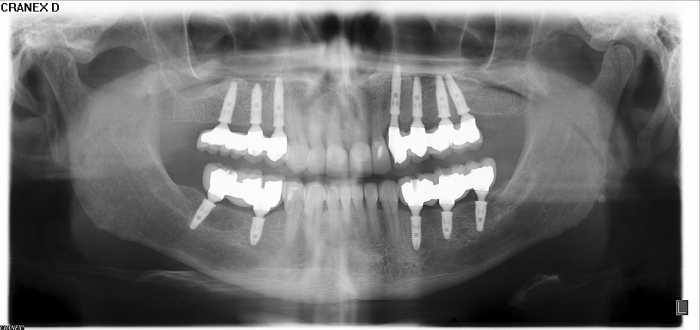

Rx Final - levantamento de seio bilateral - implantes